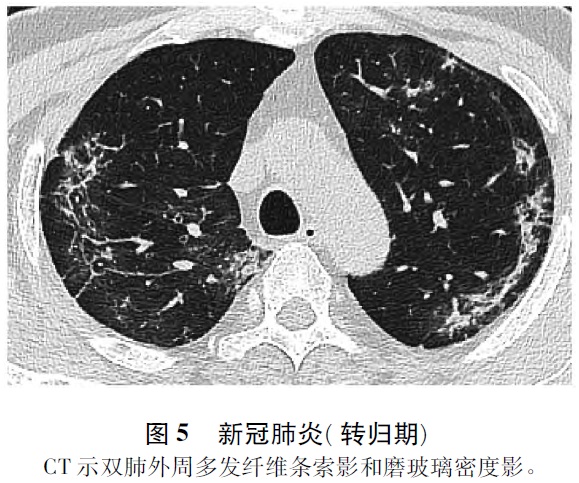

1. 4 转归期 此期患者体温下降,咳嗽次数减少,肺功能明显改善。影像表现为病变范围缩小,密度减低,渗出物吸收,肺实变病灶逐渐吸收消散,可完全消失,或残存肺纤维条索影(图5) [1-5]。